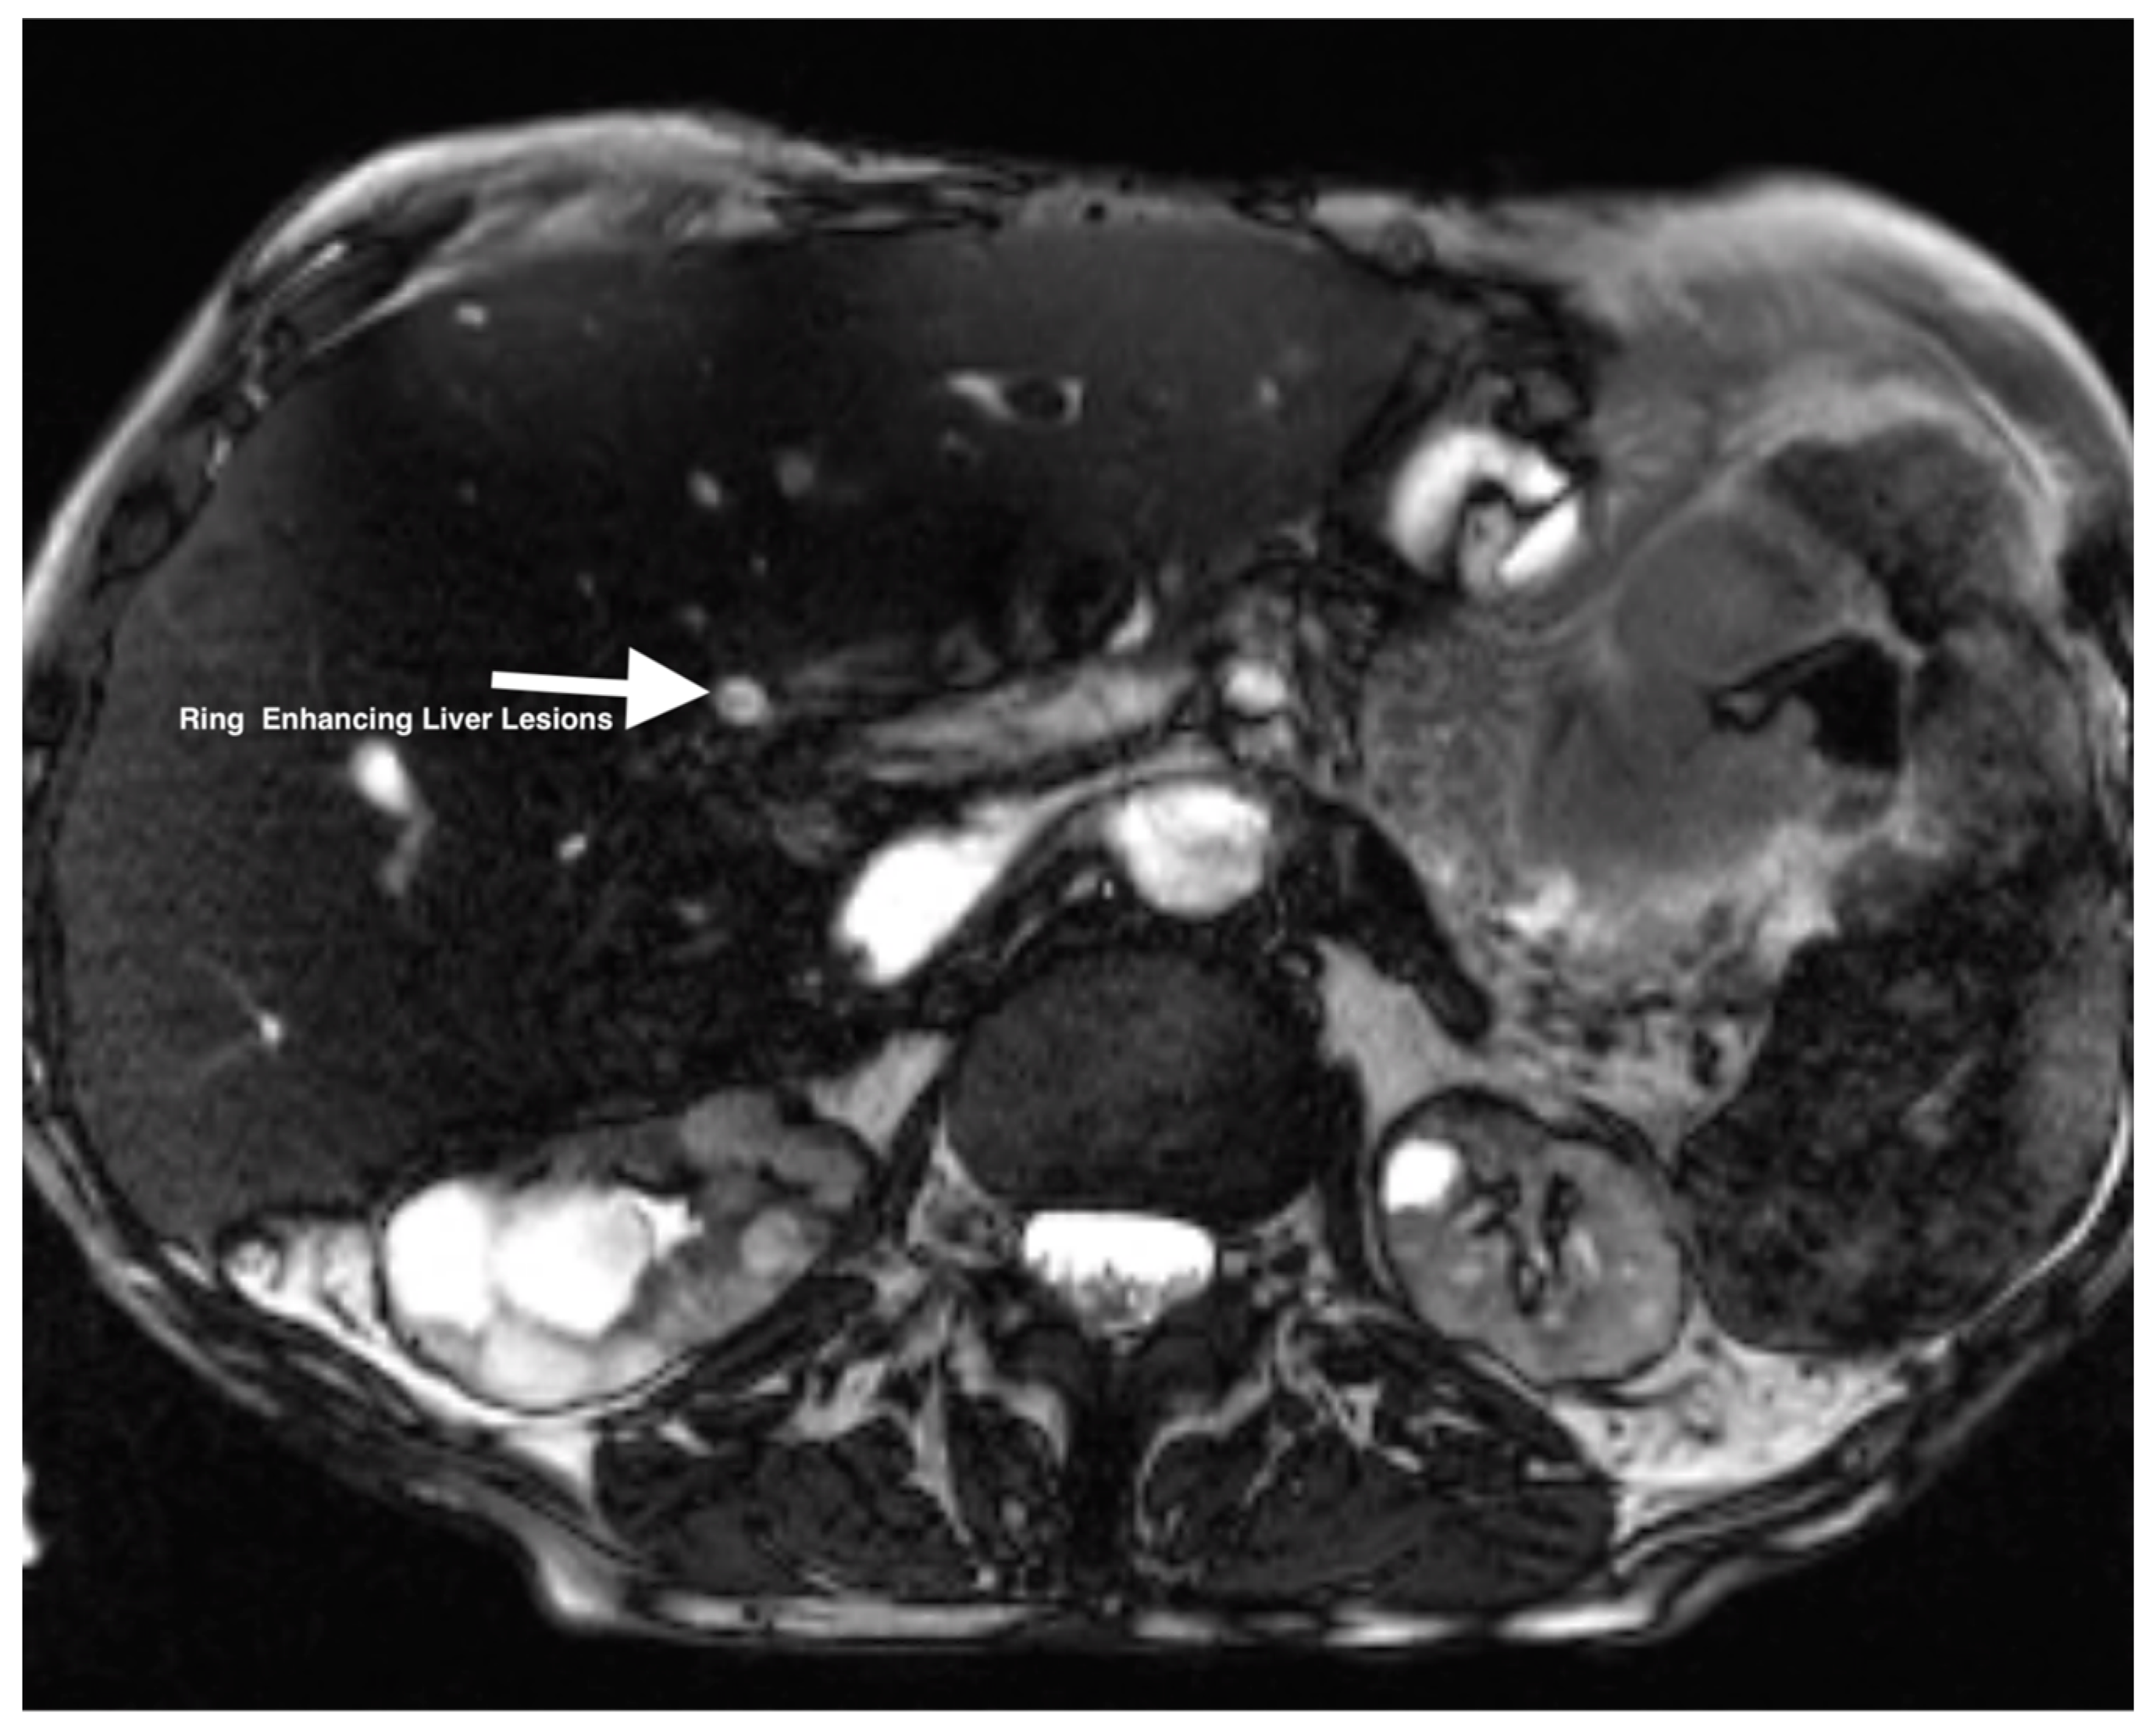

| 2 | CTA abdomen/pelvis | Focus of hyperintensity on the venous phase in the loop of jejunum suggestive of active bleeding without evidence of arterial extravasation. Multiple hypodense lesions throughout the transplanted liver. |

| 2 | US-guided liver biopsy | Consistent with adenocarcinoma with abundant necrosis and multiple clusters of bacteria within the areas of necrosis. |